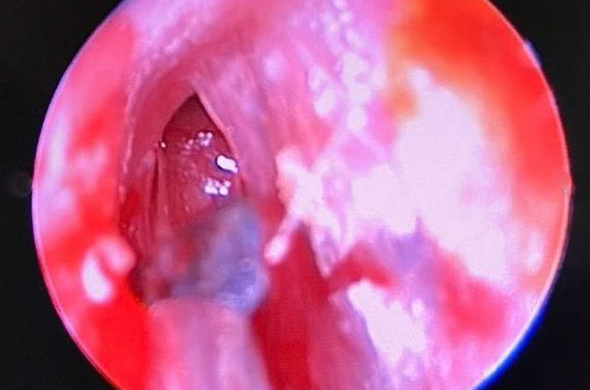

В Пензе врачи нашли за барабанной перепонкой сварщика осколок металла

В Пензе врачи клинической больницы им. Захарьина 3 марта, во Всемирный день слуха, провели уникальную операцию.

Пациент поступил в больницу с подозрением на инсульт. В процессе обследования медики увидели, что за барабанной перепонкой есть инородные тела. На снимке просматривались окалины, которые попали в ухо при сварочных работах.

— Эндоскопическая операция по извлечению металлических осколков длилась 45 минут, — сообщили в клинической больнице №6, уточнив, что операция проводилась под руководством завотделением, главного внештатного отоларинголога Андрея Федина.

Попадание окалин в ухо — не редкость для сварщиков, в первую очередь это говорит о несоблюдении техники безопасности . Обычно осколки остаются в слуховом проходе и повреждают барабанную перепонку, но не оказываются за ней.

Пациент поступил в больницу с подозрением на инсульт. В процессе обследования медики увидели, что за барабанной перепонкой есть инородные тела. На снимке просматривались окалины, которые попали в ухо при сварочных работах.

— Эндоскопическая операция по извлечению металлических осколков длилась 45 минут, — сообщили в клинической больнице №6, уточнив, что операция проводилась под руководством завотделением, главного внештатного отоларинголога Андрея Федина.

Попадание окалин в ухо — не редкость для сварщиков, в первую очередь это говорит о несоблюдении техники безопасности . Обычно осколки остаются в слуховом проходе и повреждают барабанную перепонку, но не оказываются за ней.